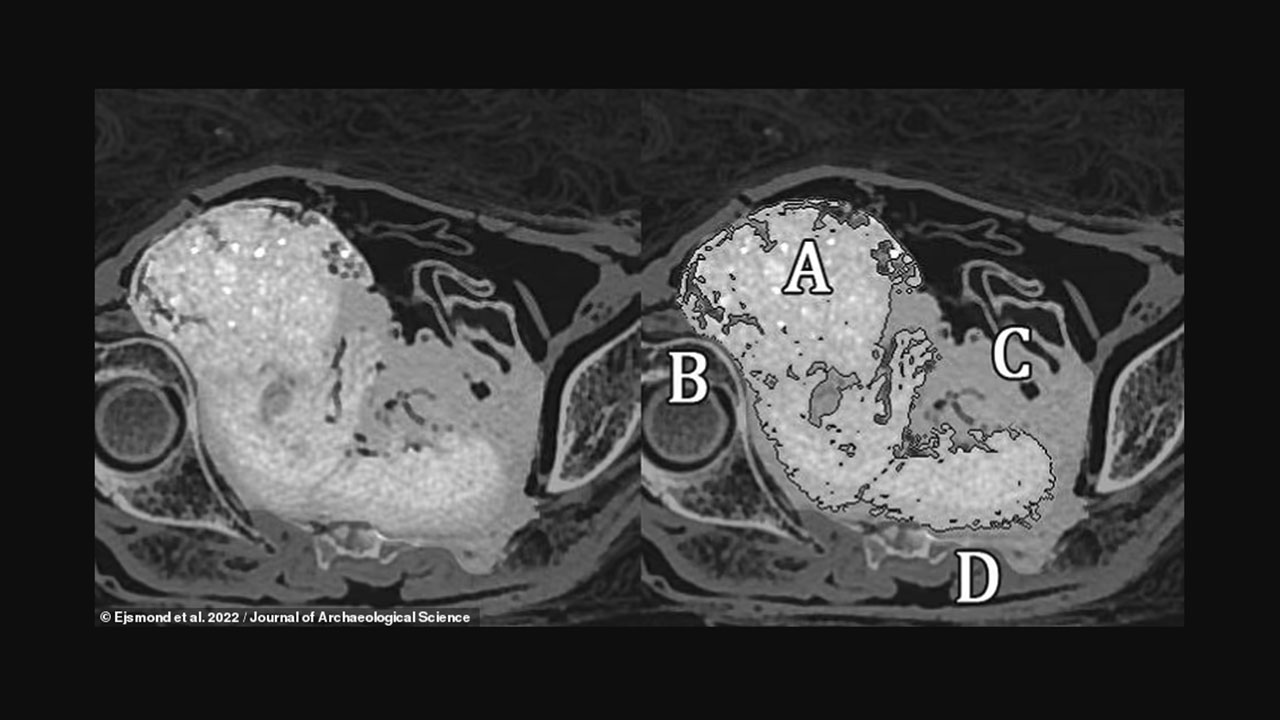

Varşova Üniversitesi bilim insanları, geçtiğimiz yıl Nisan ayında, bir mumyayı incelemeye başladı. Ekip, bilgisayarlı tomografi ve X-ray taramalarını kullanarak kadın mumyanın karnındaki doğmamış çocuğun kalıntılarını ortaya çıkardı.

Araştırmacılar, fetüsün vücudun çürürken asitlenmesiyle ‘salamura’ gibi 2 bin yıldan fazla bir süredir korunduğunu açıkladı. Bu arada bu mumyanın, bir fetüse sahip bilinen ilk mumyalanmış örnek olduğu düşünülüyor.

Araştırmacılar, fetüsün pozisyonuna ve doğum kanalının şekline dayanarak Gizemli Hanım'ın doğum esnasında ölmediğini belirledi. Önceki araştırmalar, mumyanın öldüğünde hamileliğinin 26-30. haftaları arasında olduğunu göstermişti. 'Gizemli Hanım' ve doğmamış çocuğu üzerindeki son çalışmayı, Polonya'nın Varşova Üniversitesinden arkeolog ve paleopatolog Marzena Ożarek-Szilke ve meslektaşları yaptı.

Bilim insanları, mumyalama işleminden sonra rahim içeriği de dahil olmak üzere cesetlerdeki kan pH'ının önemli ölçüde düştüğünü, daha asidik hale geldiğini ve amonyak ve formik asit konsantrasyonlarının zamanla arttığını söylüyor. Araştırmacılar, “Vücudun natron ile dolması, hava ve oksijene erişimi önemli ölçüde sınırladı. Sonuç, fetüsün bulunduğu neredeyse hava geçirmez şekilde kapalı bir rahim.” diyor. Bilim insanları, bu durumu bataklıklardaki bedenlerin yüzyıllarca korunmasına benzetti.